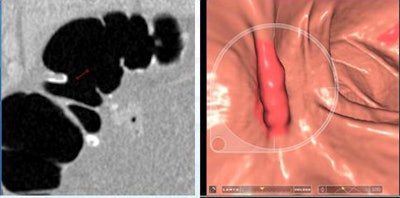

Two lesions were detected only by CAD and were not reported by the radiologists as flat due to low conspicuity. Two lesions with heights < 1 mm weren't seen at CTC but were detected at conventional colonoscopy.

| Two lesions showing a typical cigarlike appearance were detected only by CAD and were not reported by the radiologists as flat due to low conspicuity. Left to right: 2D image, 3D endoscopic view, colonoscopy view. |